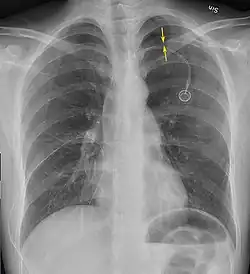

Image from a computed tomography (CT) scan of the chest. On the right (left side of the patient) there is a black area suggesting free air inside the chest

CT scan of the chest showing a pneumothorax on the person's left side (right side on the image). A chest tube is in place (small black mark on the right side of the image), the air-filled pleural cavity (black) and ribs (white) can be seen. The heart can be seen in the center.